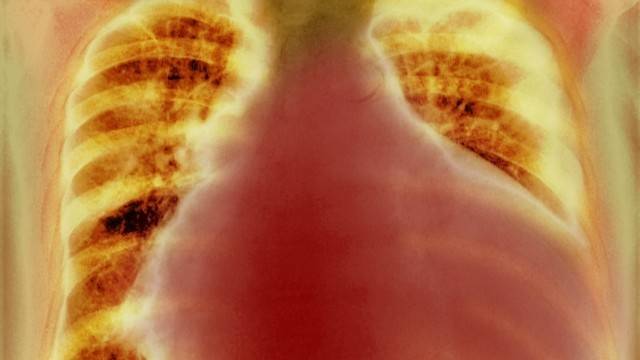

특히 자각 증상이 없는 경우가 많아, 정기적인 건강검진을 받지 않으면 발견하지 못하고 지나치기 쉽다. 심비대증은 주로 흉부 X-ray나 CT 같은 영상 검사를 통해 처음 발견되며, 영상에서 심장의 좌우 폭이 흉곽의 50%를 넘어설 경우 심장이 커져 있다고 판단할 수 있다. 이후에는 심장 초음파 검사를 통해 실제 심장 크기와 구조적 이상 여부를 정밀하게 확인하게 된다.